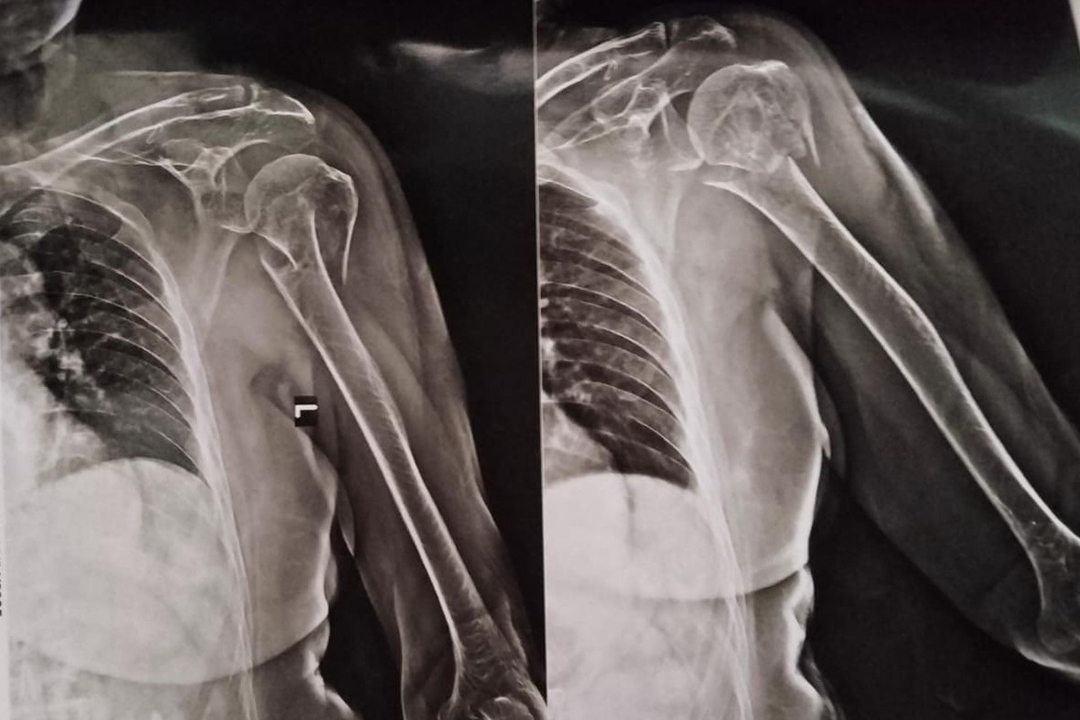

Radiographic Evaluation

Pre-operative X-ray: Displaced surgical neck fracture of proximal humerus